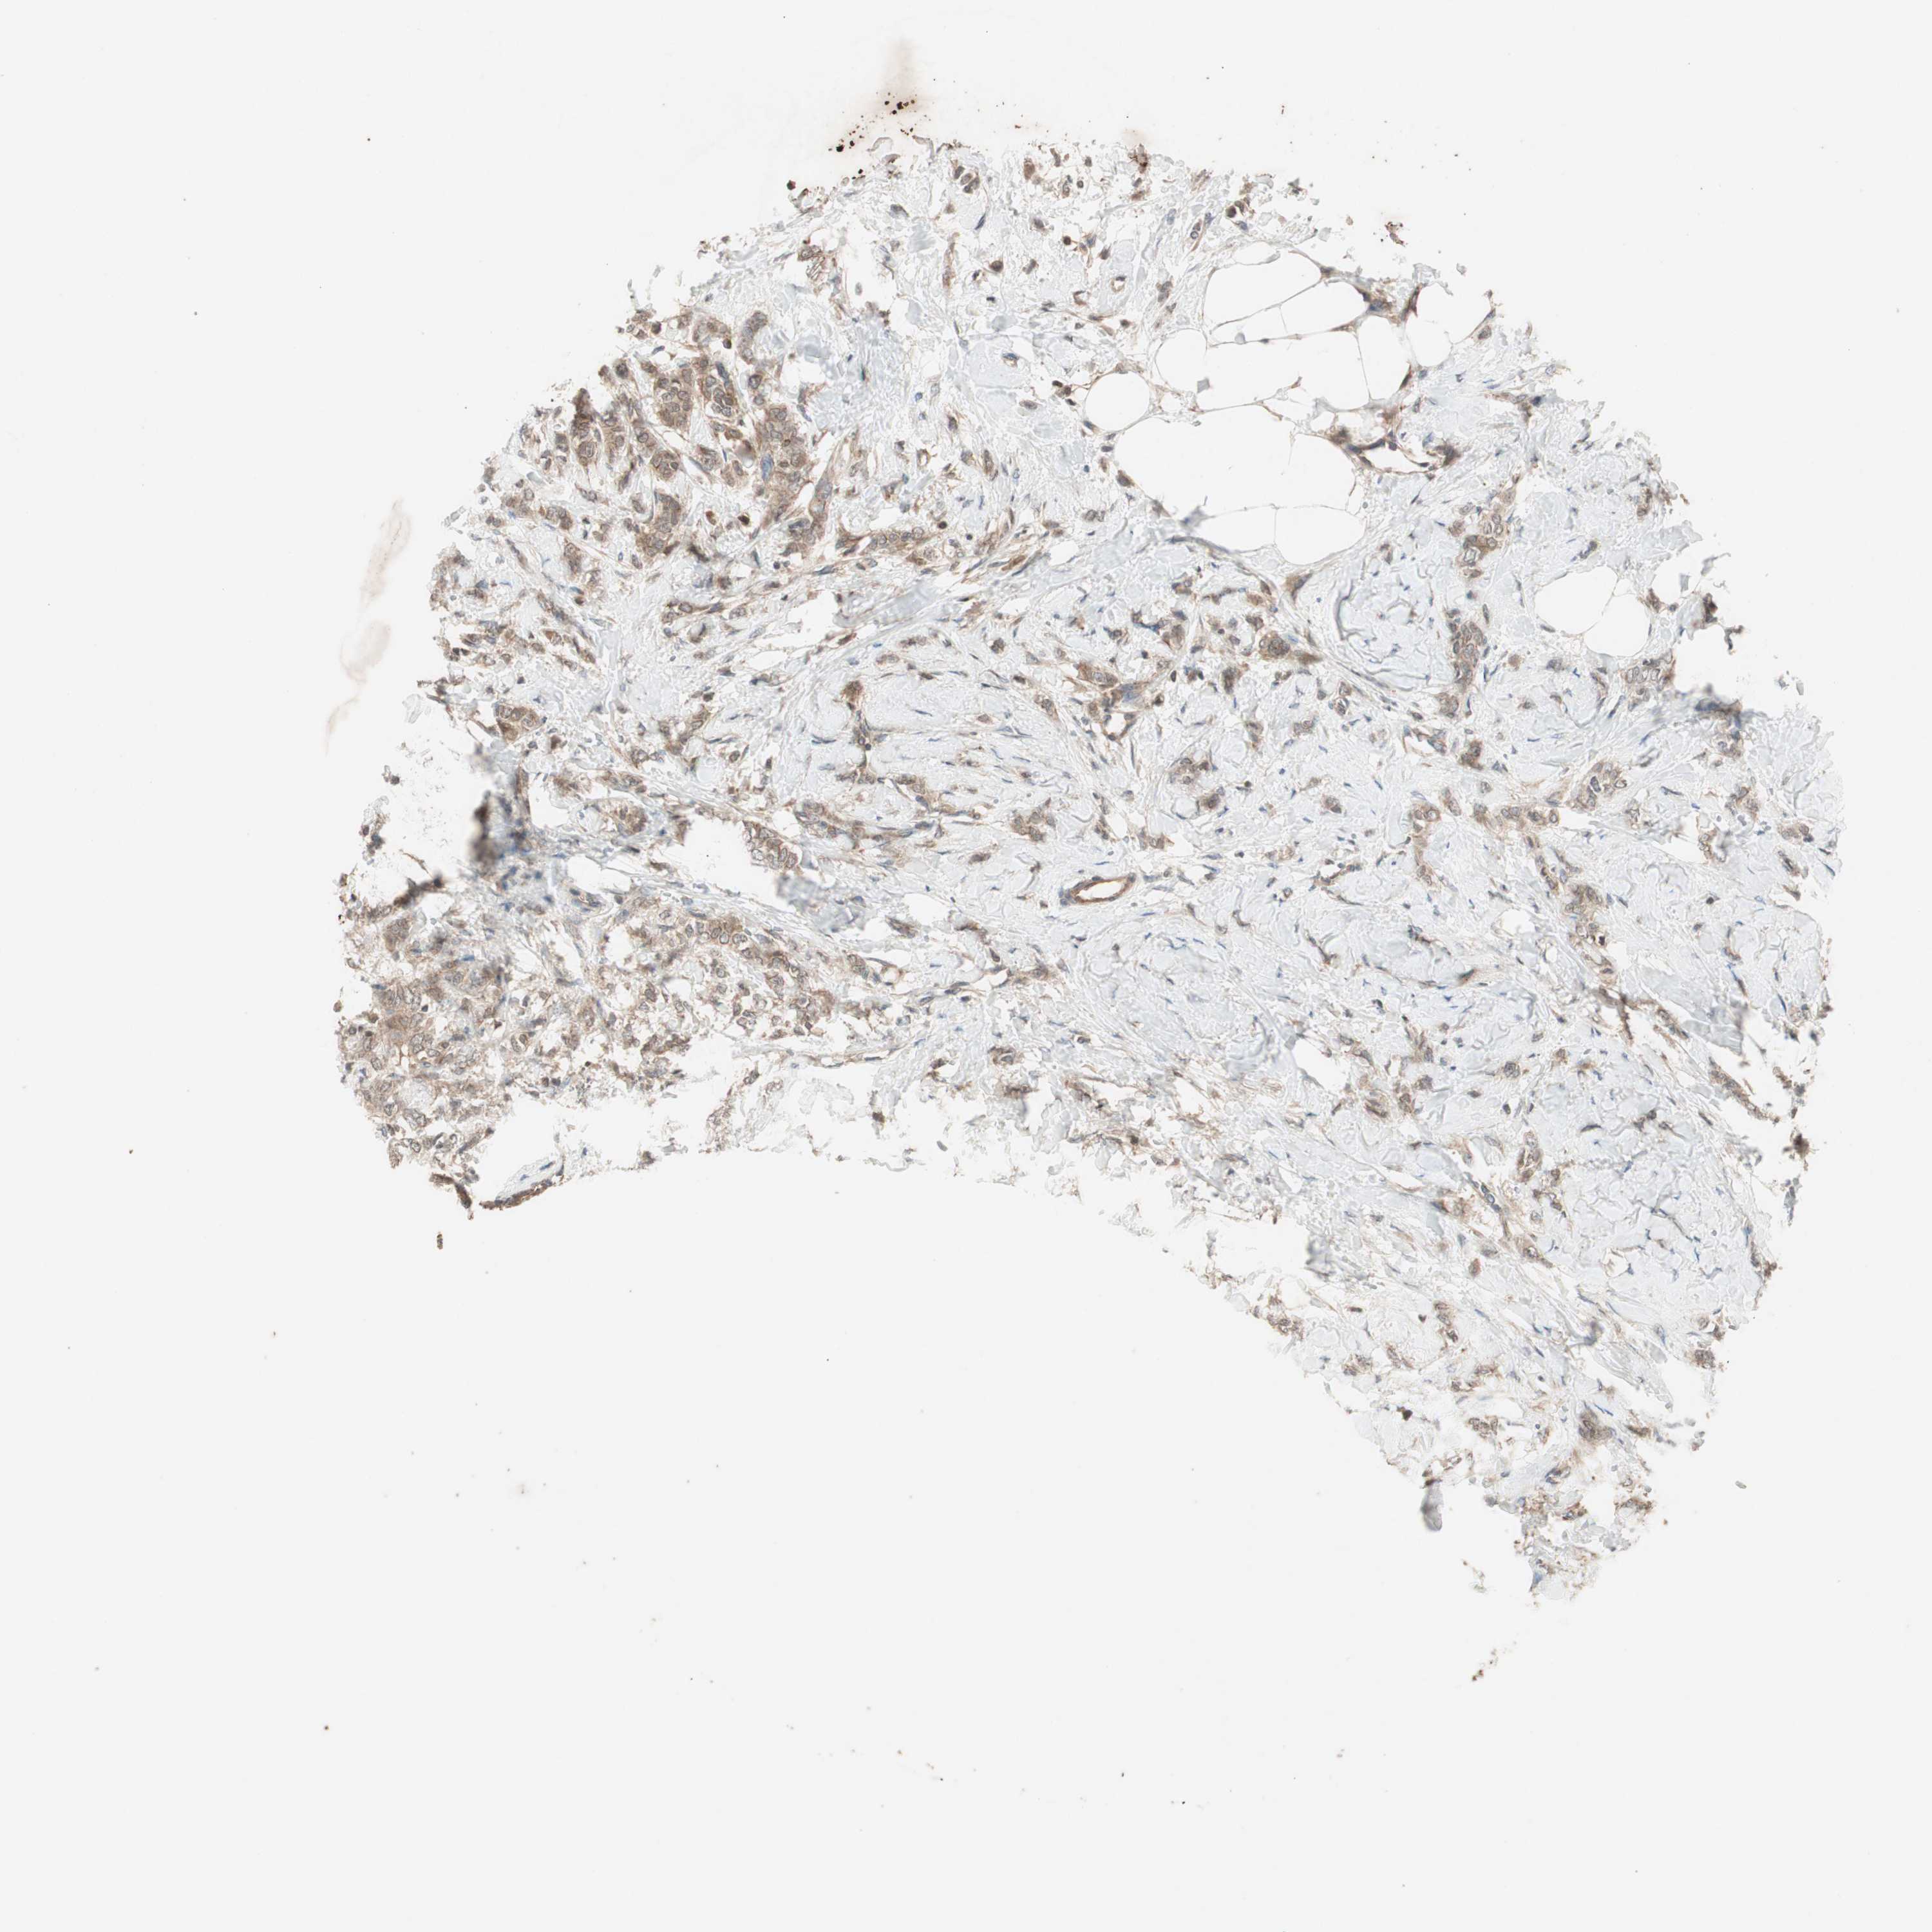

CANCER BREAST CANCER Show tissue menu

BRCA TCGA BRCA VALIDATION PROTEIN EXPRESSION

Breast cancer

Human cancer